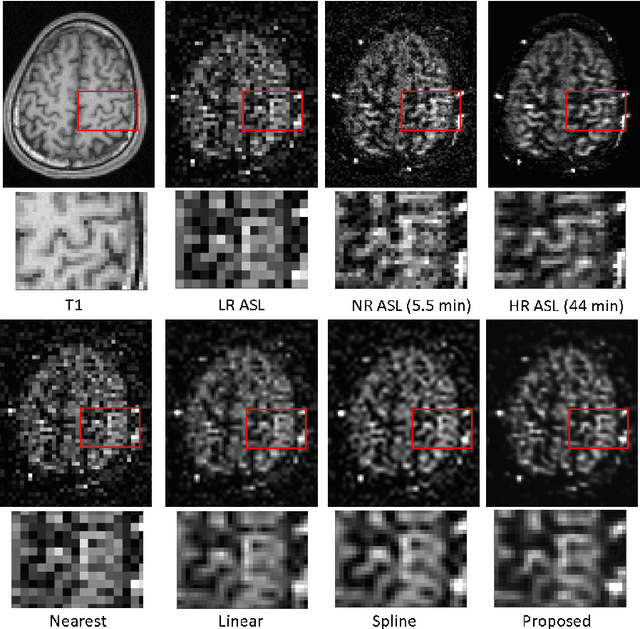

Arterial spin labeling (ASL) magnetic resonance imaging (MRI) is a powerful imaging technology that can measure cerebral blood flow (CBF) quantitatively. However, since only a small portion of blood is labeled compared to the whole tissue volume, conventional ASL suffers from low signal-to-noise ratio (SNR), poor spatial resolution, and long acquisition time. In this paper, we proposed a super-resolution method based on a multi-scale generative adversarial network (GAN) through unsupervised training. The network only needs the low-resolution (LR) ASL image itself for training and the T1-weighted image as the anatomical prior. No training pairs or pre-training are needed. A low-pass filter guided item was added as an additional loss to suppress the noise interference from the LR ASL image. After the network was trained, the super-resolution (SR) image was generated by supplying the upsampled LR ASL image and corresponding T1-weighted image to the generator of the last layer. Performance of the proposed method was evaluated by comparing the peak signal-to-noise ratio (PSNR) and structural similarity index (SSIM) using normal-resolution (NR) ASL image (5.5 min acquisition) and high-resolution (HR) ASL image (44 min acquisition) as the ground truth. Compared to the nearest, linear, and spline interpolation methods, the proposed method recovers more detailed structure information, reduces the image noise visually, and achieves the highest PSNR and SSIM when using HR ASL image as the ground-truth.